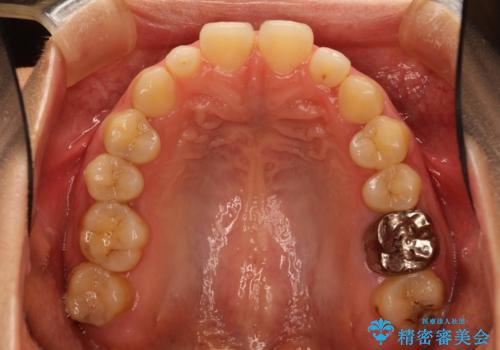

Invisalign インビザライン lite ライト 隙っ歯の改善

- マウスピース矯正による隙間の閉鎖を計画しました。

簡便な処置のため、ライトを選択しました。

かみ合わせが深くない空隙歯列は、最も簡単にその改善が見込まれます。